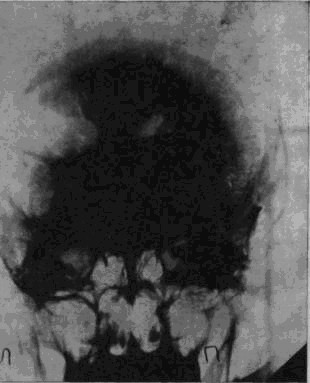

![]() |

Рис. 1а. Рентгеновский снимок черепа больного Засецкого после введения воздуха в желудочки мозга (пнеймоэнцефалограмма). На нем можно видеть резко расширенный левый боковой желудочек и скопление воздуха в подоболочечных пространствах мозга теменно-затылочной области левого полушария

Осколок внедрился в вещество задних, теменно-затылочных отделов мозга и разрушил мозговую ткань этой области.

Ранение осложнилось воспалительным процессом; он не распространенный, местный, ограничен лишь областями мозга, примыкающими к непосредственному месту ранения, но теменно-затылочные отделы левого полушария, отделы, так тесно связанные с анализом пространственного мира, необратимо повреждены, и уже начинается процесс образования рубцов, который неизбежно повлечет за собою частичную атрофию расположенных вблизи ранения участков мозгового вещества.

И через десять лет после ранения – еще одна выписка из истории болезни, на этот раз сделанная на основе рентгенограммы.

В спинномозговой канал введен воздух. Он поднялся вверх, заполнил контуры желудочков мозга и те пустоты, которые образовались в результате сморщивания вещества отделов мозга, непосредственно примыкающих к месту ранения. «Процесс рубцевания вызвал атрофические изменения в левом боковом желудочке. Стенки его подтянуты к поверхности мозга, подоболочечные пространства резко расширены. Значительный местный атрофический процесс».

Ранение вызвало местную атрофию мозгового вещества левой теменно-затылочной области.